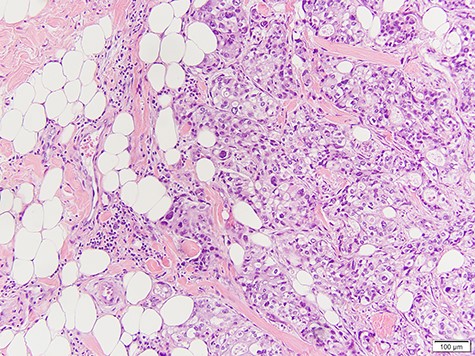

She underwent surgical excision of the breast mass. Final pathology confirmed poorly differentiated carcinoma morphologically identical to her known parotid adenocarcinoma (Fig. 2).

Infiltration of high-grade poorly differentiated malignant cells from breast biopsy.